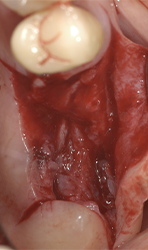

Maximum preservation of the alveolar housing and related gingival structures may be achieved following assisted atraumatic tooth extraction by an electrical mallet (Fig. 3).

Different thin metallic blades may be connected to the Magnetic Max handpiece, sending a magnetic wave on the tip. The Magnetic Max imparted to blade a longitudinal movement along the central axis, moving up and down between root surface and lamina dura of the alveolus in a repetitive circumferential fashion, providing a driving mechanism of longitudinal movements. This movement also allows the maintenance of lamina dura for wisdom teeth (Figs. 4a-4c).